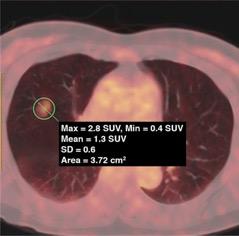

62-year-old woman with pure ground-glass nodules (GGN). PET/CT fusion image shows pure GGN with tumor maximum standardized uptake value of 2.8 (circle).

62-year-old woman with pure GGN. PET/CT fusion image shows pure GGN with tumor maximum standardized uptake value (SUVmax) of 2.8 (circle).

Additionally, SUVmax was higher in invasive adenocarcinoma than in adenocarcinoma in situ (AIS)–minimally invasive adenocarcinoma (MIA), with SUVmax 2.0 the optimal cutoff value for differentiation.

Acinar-papillary adenocarcinoma had a higher SUVmax than lepidic adenocarcinoma, with SUVmax 1.4 the optimal cutoff value for differentiation.